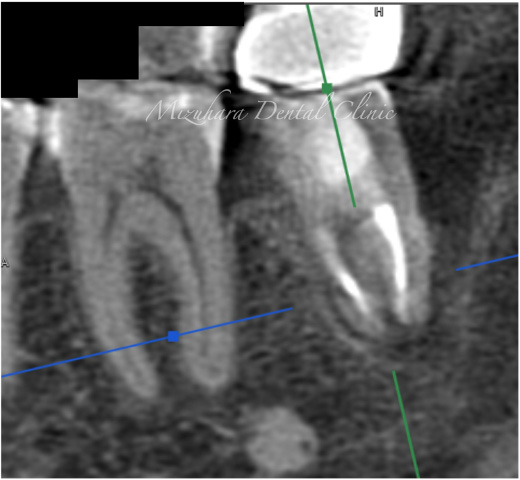

| 主訴 | 左下の奥歯が腫れて、揺れてる。 抜歯するしかないと言われたが、他に方法がないか相談したい。 |

| 治療内容 | 精密根管治療 再生療法 (歯周病によって骨が無くなった部分に骨を足す治療) 被せ物:オールセラミッククラウン |